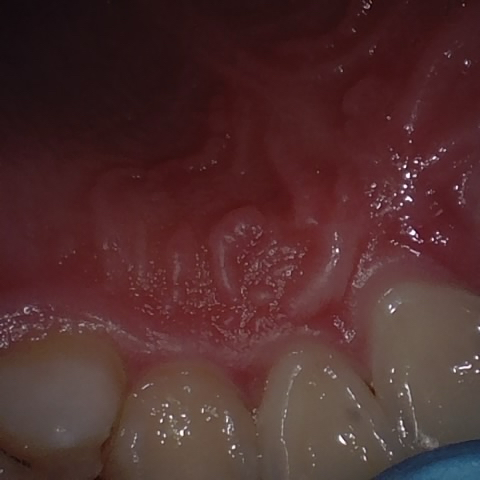

Annotated as "Good"